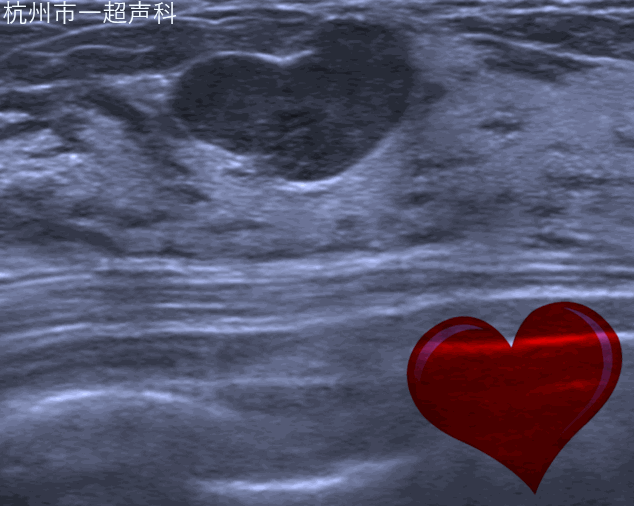

我院超声科开展乳腺超声多模态诊断,包括自动乳腺容积超声、弹性成像、超声造影以及乳腺结节融合成像虚拟导航。

自动乳腺容积超声应用宽幅高频探头的自动扫描实现乳腺全容积的规范化图像,减少漏诊;独特的冠状面对鉴别诊断提供了三维的信息。自动乳腺容积超声对早期乳腺癌的影像学诊断,乳腺结节的BI-RADS分类评估,乳腺肿瘤的临床分期,新辅助化疗的疗效评估,乳腺癌的筛查有明显的优势。超声影像科于2010年在省内率先开展该项技术,也是国内最先开展的333体育 之一。目前无论在累积的病例数还是诊断水平均属国内领先。2018年,我们完成30000例病人的基础上在国内发布首个自动乳腺全容积成像系统操作流程,为行业制订检查规范。团队发表包括SCI在内333体育相关的文章40余篇,在RSNA及WFUMB等国际会议发表研究结果,开展全国的多中心研究,与知名院校的产学研合作。每年举办国际级继续教育学习班,作为培训基地,为全国各大333体育 培训医生200余人。加强国际交流,每年接待来自欧美、亚太地区的专家进行学术交流与合作。